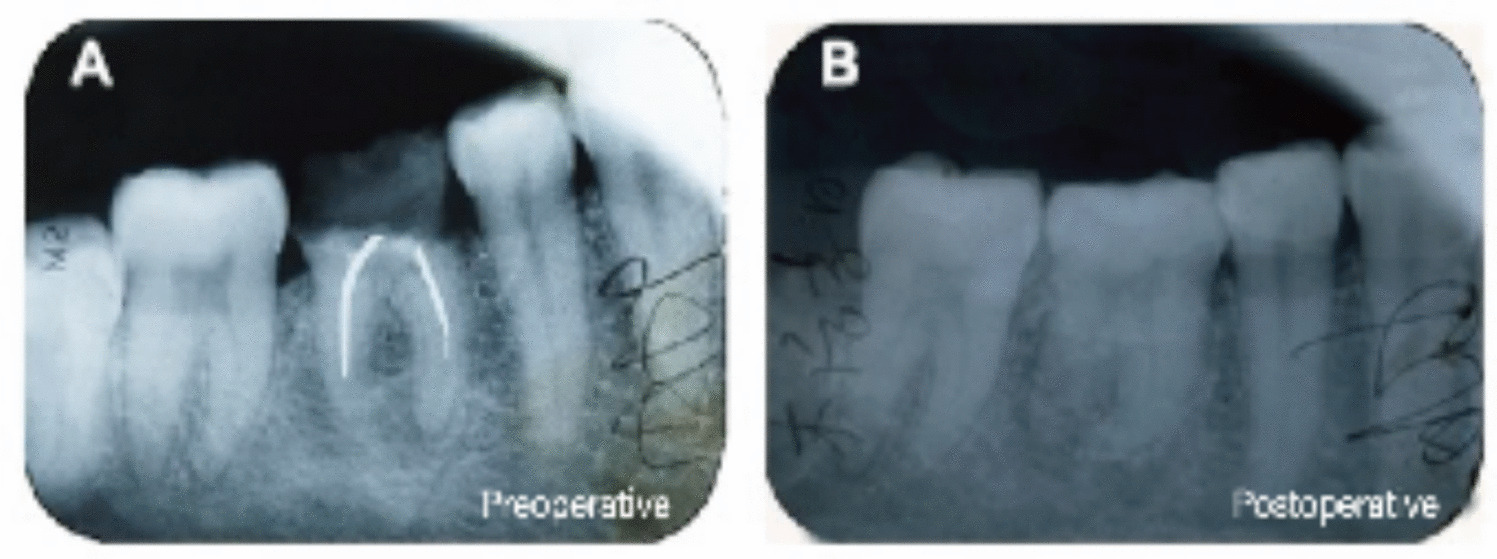

Longitudinal monitoring of the transplanted dentition was maintained for two decades postoperatively. At the 6-year follow-up interval, carious lesions were identified in the grafted teeth and managed through composite restorations. The most recent assessment demonstrated successful osseointegration of tooth 46 with no detectable mobility, accompanied by physiologically responsive pulp status confirmed via thermal sensitivity testing. While the occlusal relationship did not attain Angle Class I standards, the tooth maintained functional occlusal stability with biomechanically favorable loading characteristics (Fig. 17).

Fig. 17

A one week postoperative (periapical dark shadows) (B) six years postoperative (apices not yet completely closed, continuous regular black translucent images surrounded the roots) (C) twelve years postoperative (apices completely closed, visible periapical space) (D) twenty-one years postoperative (intraoral photograph) (E) twenty-one years postoperative (intraoral photograph) e: twenty-one years postoperative (adequate centric occlusal contact position)